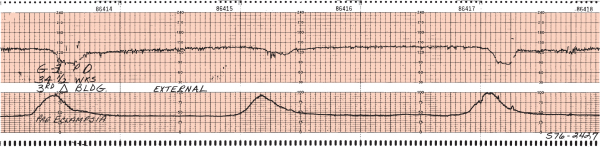

aceler.png

brad.png

des prec.png

des tard.png

des var.png

fcf_norm.png

taq.png

variabilidad.jpg

variabilidad_reducida.jpg